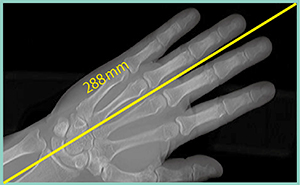

なお,体軸方向160mmの撮影範囲内に被写体を斜めに配置することで,約280mmの撮影が可能となる(図2)。

図2 エリアファインダ使用時の撮影範囲を

最大限に生かすポジショニング